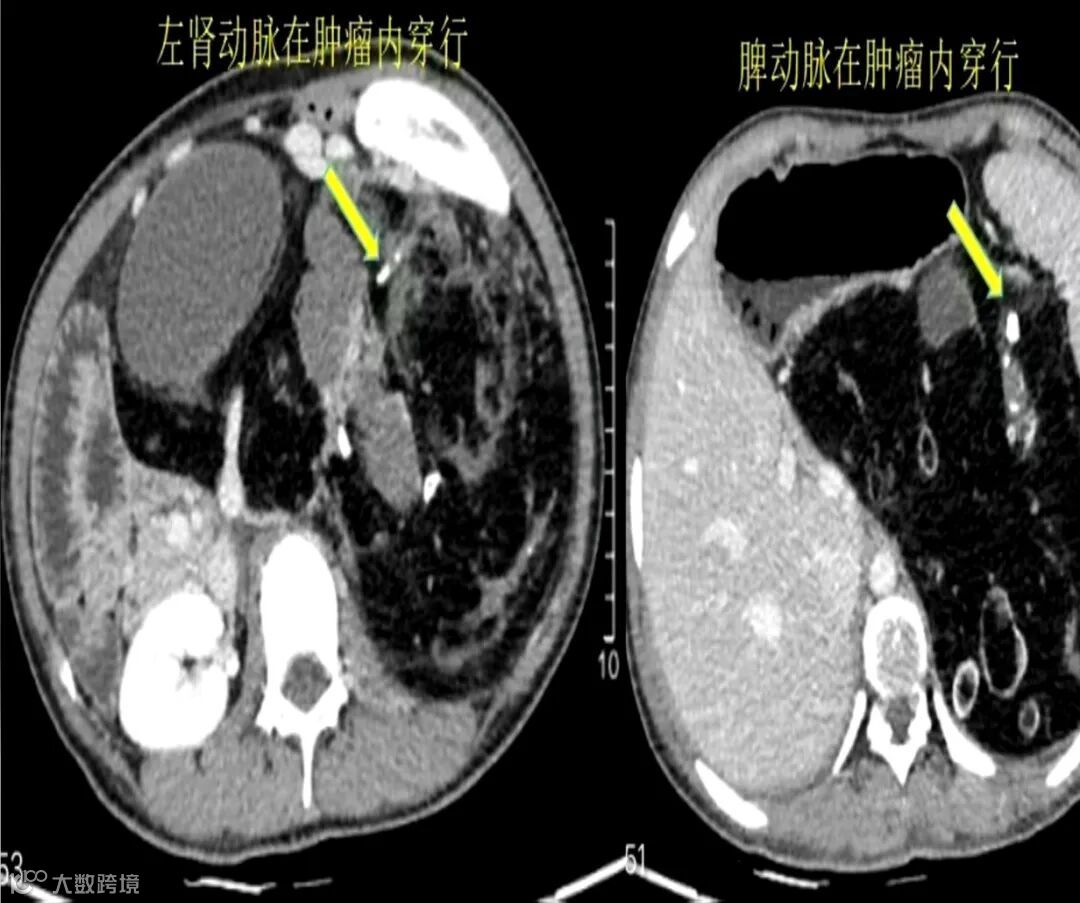

云南省第三人民医院肝胆胰外科主治医生 陈伟:“主要是两点,一个是肾动脉和脾动脉在肿瘤里边穿行,当时也和家属及她本人谈过,有可能她肾脏和脾脏都要放弃,为了切除这个肿瘤嘛。然后手术当中也是在肿瘤里边把它穿行的血管给剥出来了,所以还是把她的脏器都保留了。她肾动脉是被肿瘤侵蚀在里面,那一段我们是做了切除,然后给她重建了,最终还是把她的脏器功能保留了。”